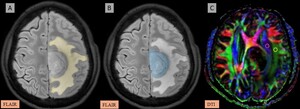

Assessing glymphatic dysfunction using the diffusion tensor image analysis along the perivascular space (DTI-ALPS) index in gliomas and metastases

Dhanush Jayanna, Shravan Reddy Kankara, Shreyas Reddy K, Arpitha Josephine, Vilas Melrick Tellis, Meghana Kancharla, Aaral Alisha Monteiro, Sunitha Palasamudram Kumaran, Saikanth Reddy Deepalam

Pol J Radiol, 2025; 90: 611-620